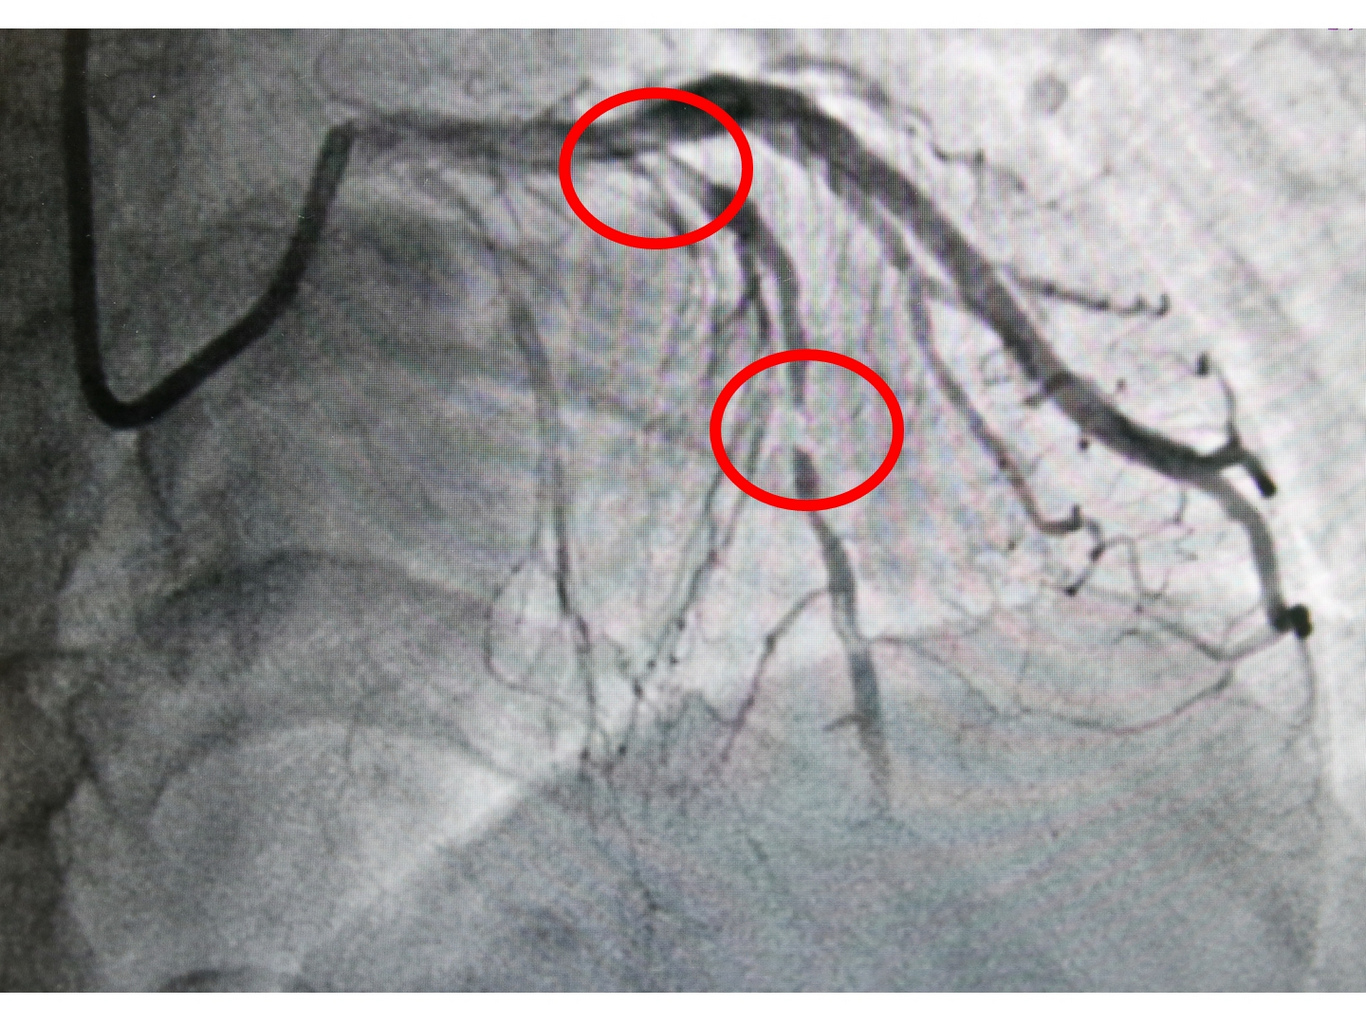

後來在一位同樣有背痛症狀的朋友建議下,張女士找到了花蓮慈院張懷仁醫師。張懷仁醫師表示,一開始很難診斷有心臟方面的問題,但是張女士提到說自己有胸悶的狀況,而且是對話一陣子就要停下來喘氣,讓張懷仁醫師擔心會不會真的是心血管的問題,結果安排心導管檢查後發現,張女士三條冠狀動脈血管中的左前降支,幾乎是完全阻塞,立即為張女士進行治療,並且放置兩條冠狀動脈血管支架。